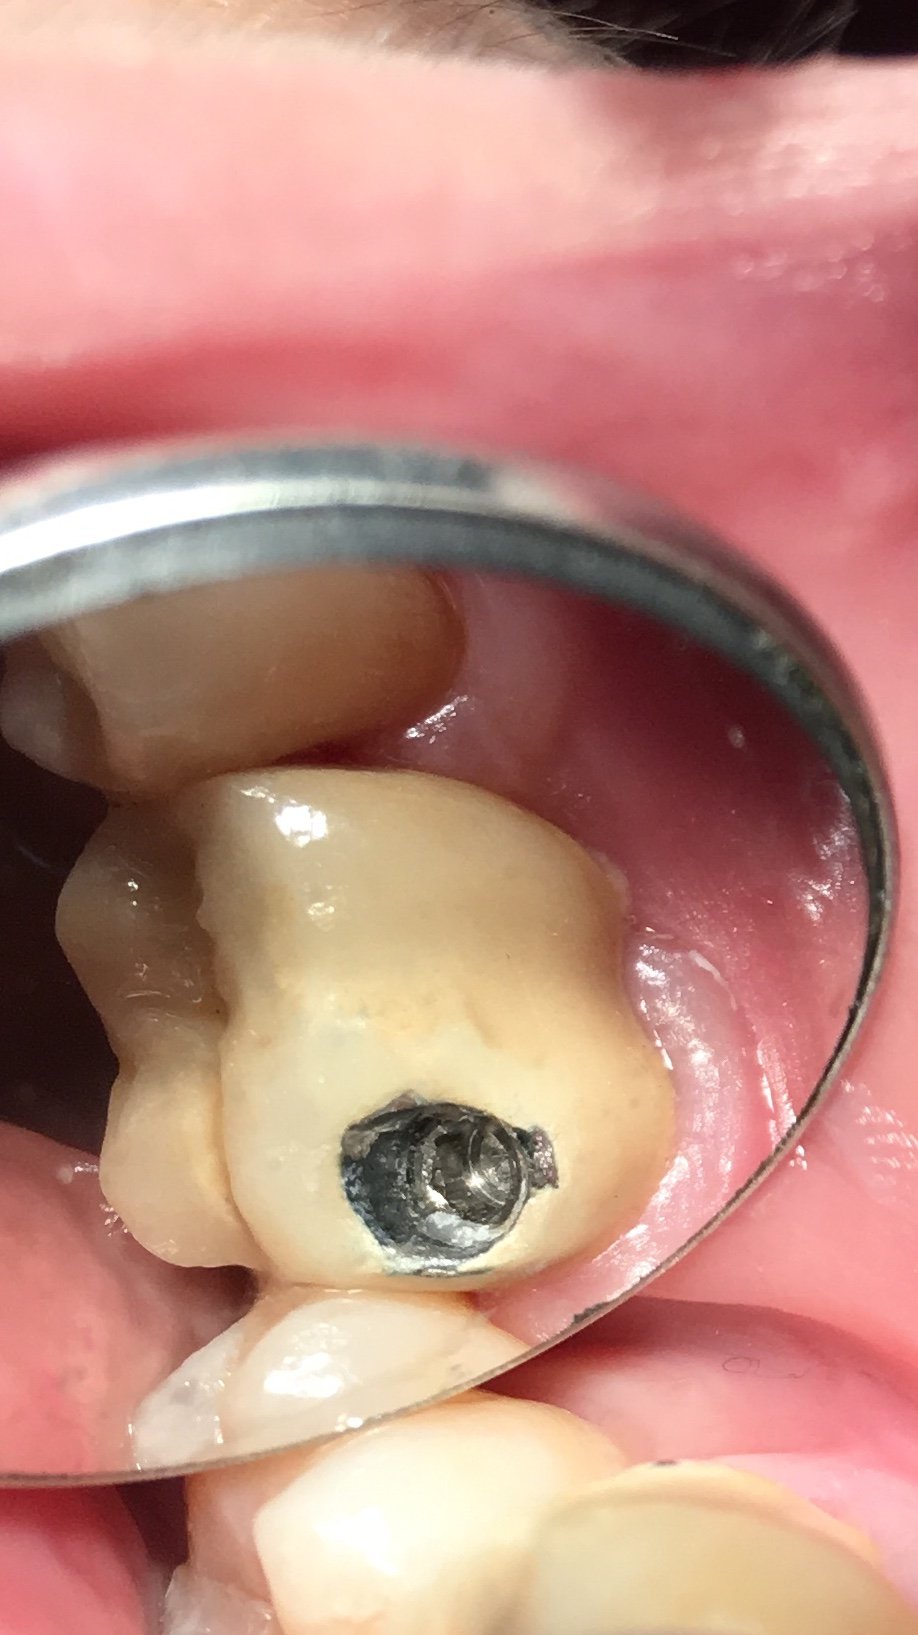

Buen día chicos. tengo este pac. El cual lleva dos IOI y presumo que son Klockner conexión cónica interna, pero no estoy segura. Llevan un transepiteliale recto, pero el transfer [...]

se han roto los tornillos de conexión y necesito cambiar